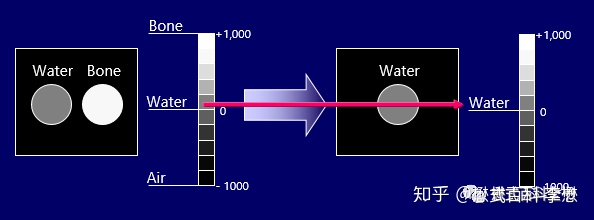

CT图像主要反映不同组织的密度高低。可以根据这个人为设定一个CT值。CT值越高,代表组织密度越大,在CT图像中越白(越亮);CT值越低,代表组织密度越小,在CT图像中越黑(越暗)。